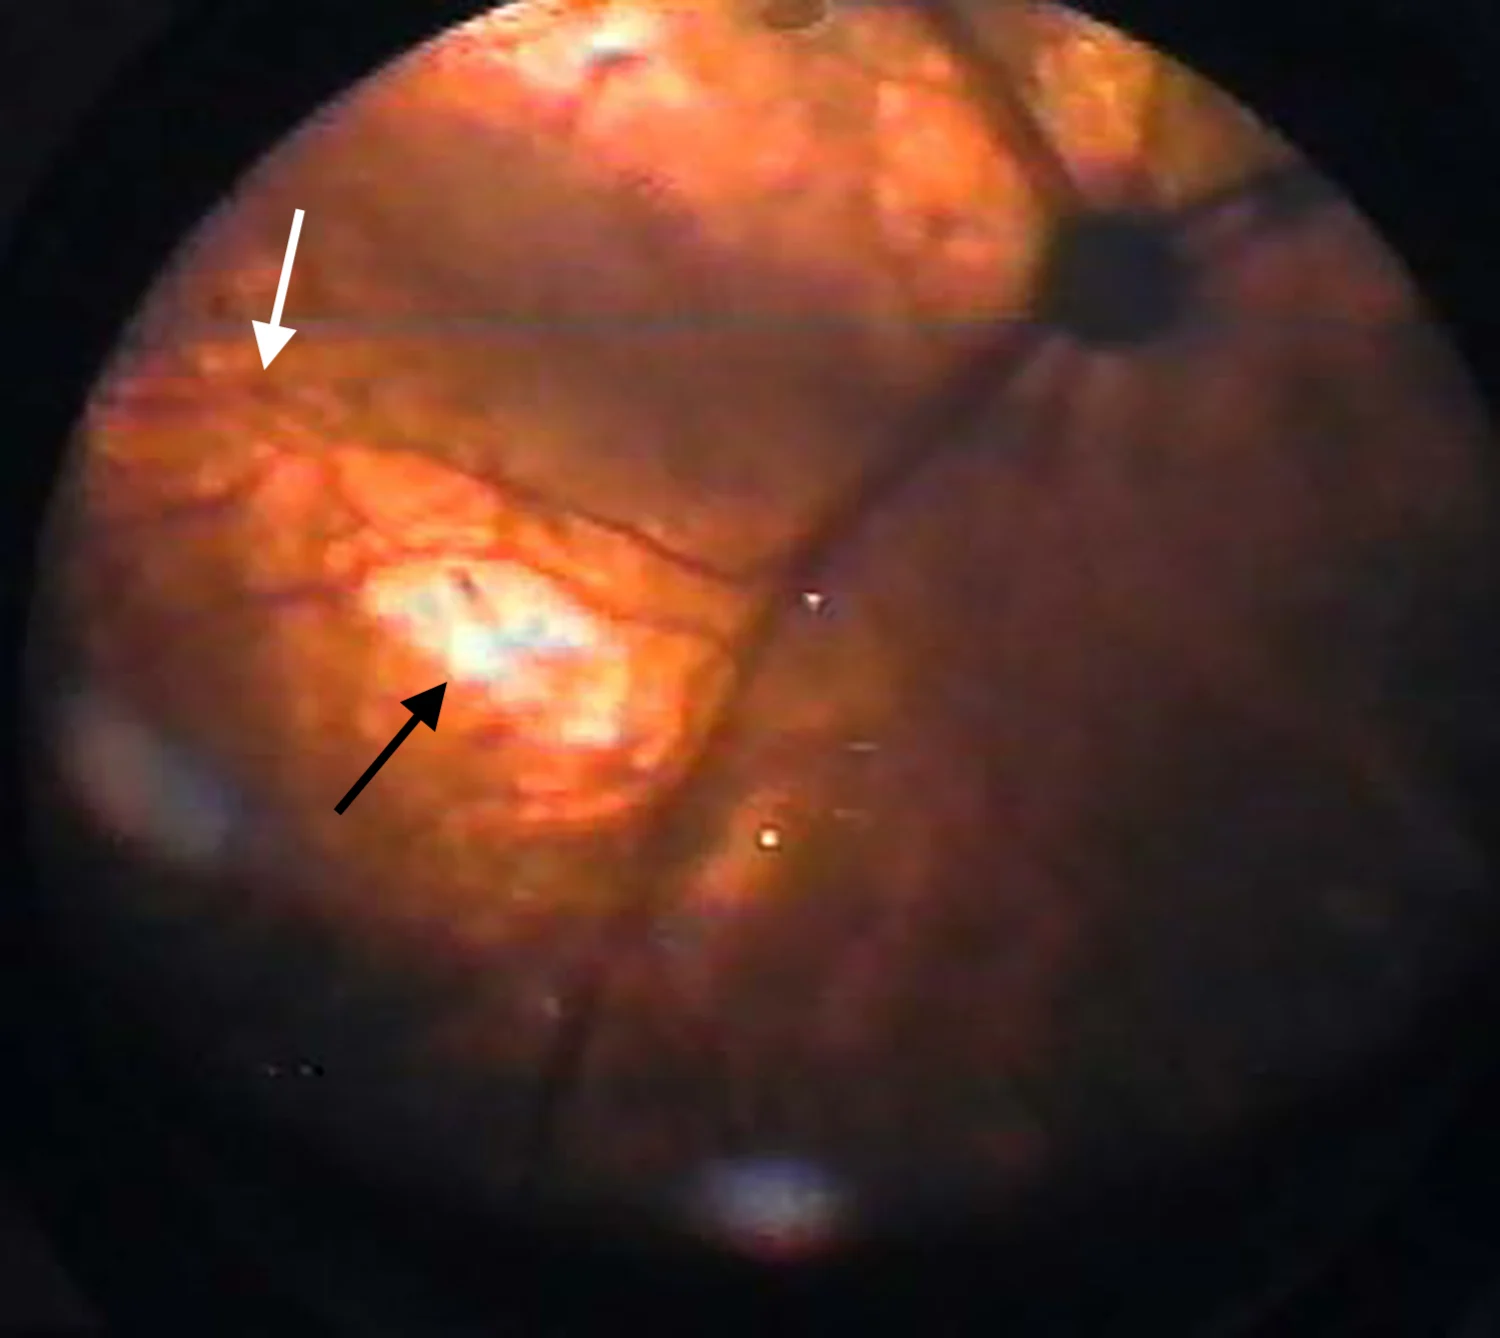

Mydriasis is typically the initial sign of retinal degeneration, but fundic signs can include tapetal hyperreflectivity, retinal vessel attenuation, increased tapetal reflectivity, and optic nerve atrophy (Figures 1 and 2). Although some affected cats regain vision, others are permanently blind.

Retina of a 16-year-old cat with chronic kidney disease that became blind following enrofloxacin administration. The fundus shows tapetal hyperreflectivity (black arrow) and attenuation of retinal vessels (white arrow). Image courtesy of Anne Metzler, DVM, MS, DACVO